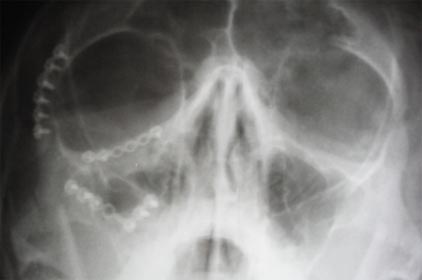

Muitas vezes o paciente apresenta problemas combinados associando a mandíbula e a maxila, por exemplo: o excesso de crescimento mandibular (mandíbula grande) e a falta de crescimento maxilar (a maxila para trás) necessitando operar os dois segmentos Saiba mais